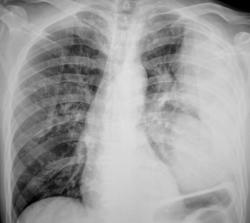

Иллюстрации 3, 4. Справа определяется почти диффузное усиление, обогащение и деформация легочного рисунка, на фоне чего дифференцируются очаговоподобные тени, округлые мелкие просветления. Тень правого корня полностью нивелирована, смещенным вправо средостением.